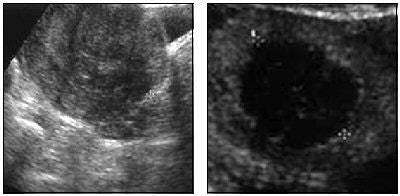

| A 42-year-old woman with menorrhagia and pelvic pain due to 4.6-cm uterine myoma. Left, suprapubic sonogram shows hypoechogenic intramural myoma. Right, contrast-enhanced sonogram after radiofrequency ablation shows anechogenic avascularized round area (treated myoma) surrounded by normal vascularized myometrium confirming success of ablation and absence of myometrial injury. Recaldini C, Carrafiello G, Lagana D, Cuffari S, Bergamini V, Ghezzi F, Fugazzola C, "Percutaneous Sonographically Guided Radiofrequency Ablation of Medium-Sized Fibroids: Feasibility Study" (AJR 2007; 189:1303-1306). |

The research began with six women (median age of 41.2) undergoing preoperative suprapubic and transvaginal sonography to assess the number, size, and location of myomas. All the patients had one symptomatic uterine myoma each. The median volume was 58.57 cm3 and the median diameter was 4.87 cm.

Percutaneous RFA (RF3000 Generator, Boston Scientific, Natick, MA) was performed under moderate sedation. The target temperature in the tissue was set at 85° C. Contrast-enhanced, microbubble-specific suprapubic ultrasound (Sonovue, Bracco Diagnostics, Princeton, NJ; Technos MPX, Esaote Biomedica, Genoa, Italy) was used as a real-time guide for the transabdominal procedure. The operative time came in at a median of 20 minutes.

The mean follow-up period was nine months and included transvaginal sonography as well as quality-of-life (QOL) questionnaires. According to the results, no repeat intervention was needed during the follow-up period. Based on the last follow-up visit, the median fibroid volume was reduced to 8.07 cm3 while the median diameter shrunk to 2.3 cm. The median QOL score 63.92.

The authors offered several take-home messages from this preliminary study. First, patients with myomas larger than 6 cm -- or multiple myomas -- are ineligible for this single-procedure technique. Also, the use of contrast-enhanced sonography offers precise targeting in highly vascularized areas, in addition to depicting changes in tissue echotexture during the procedure. Finally, interventional radiologists are best-suited to perform this procedure as accessing superficial as well as deep organs is highly operator-dependent.